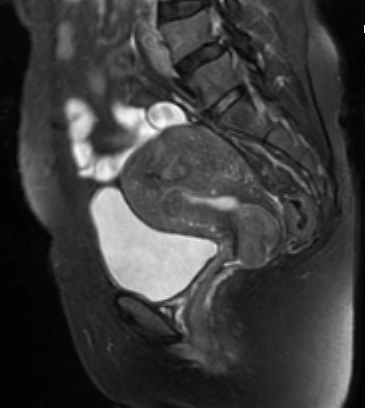

U xơ tử cung ở cổ tử cung (Leiomyoma of the uterine cervix)

16/03/2026